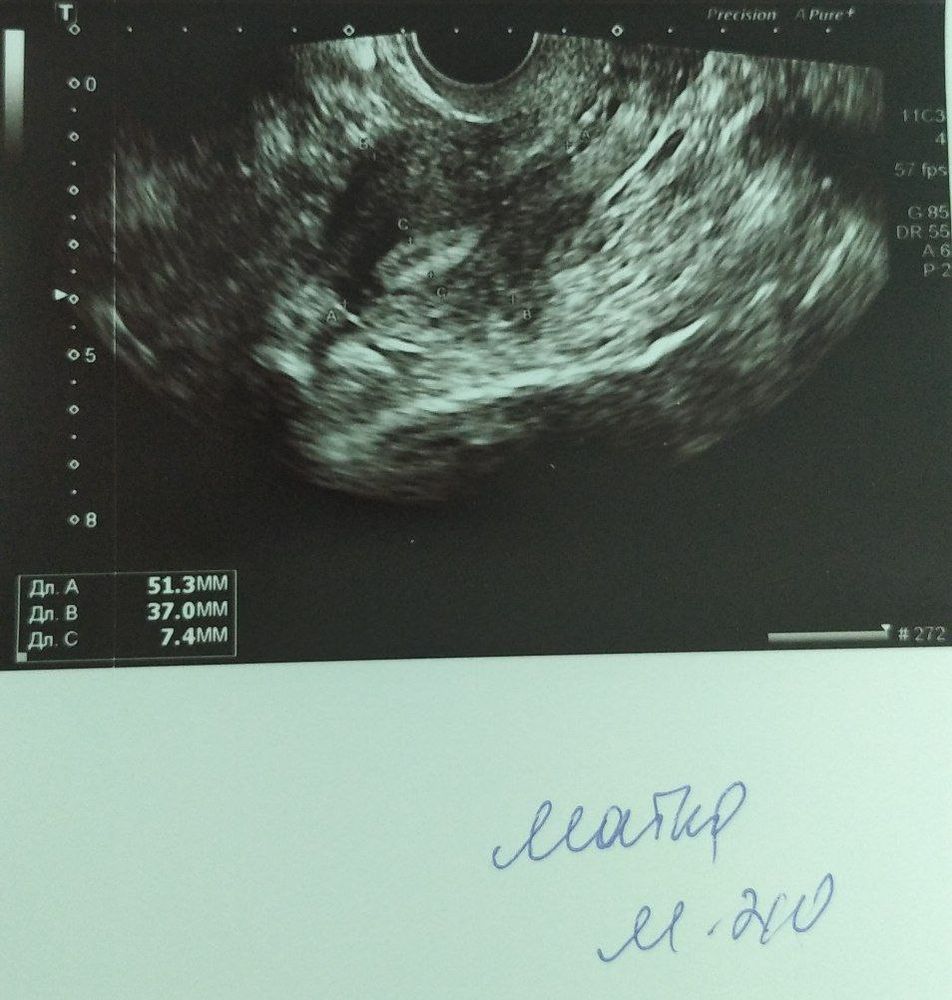

Мария , выкидышей не было, но в первую беременность принимала какое-то время. Насколько я помню был риск отслоения плаценты. Хотя эта врач то об этом не знала. Вы думаете есть шанс забеременеть с таким эндометрием? 7,4 мм у меня как я понимаю

Екатерина, есть, но я ничего не понимаю в них

Lisa, прикрепите фото узи. Будет понятнее, что не так. Девочки тут есть опытные. а дюфастон - это любимая их схема. Но не всем подходит. Я отказалась от него, так как у меня овуляция обычно поздняя и на нем ее вообще не было бы.

Изображение Екатерина, 19 день цикла

Изображение Екатерина, да, вот

Lisa, ничего плохого не вижу. Эндометрий 7,4мм тоже годится для зачатия. И советую пить дюфастон после овуляции. Отслеживать ее по тестам например, если на узи денег жалко.